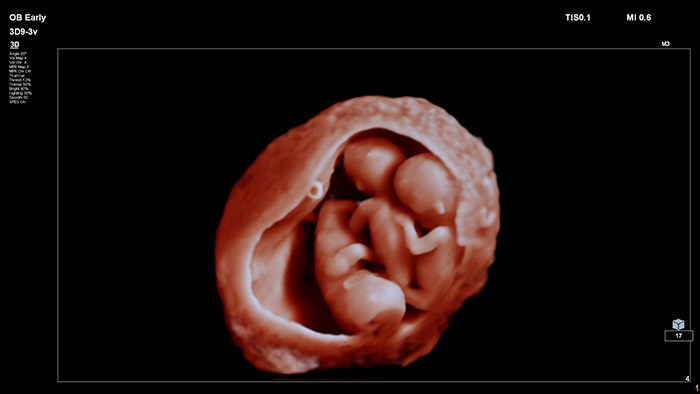

Neste vídeo, o Dr. Michael Ruma apresenta o transdutor 3D de ultrassons V9-2 da Philips. O V9-2 é o primeiro transdutor mecânico 3D PureWave de ultrassons da Philips para obstetrícia/ginecologia que oferece uma excelente qualidade de imagem e um design ergonómico avançado. O V9-2 é extraordinário em imagiologia 2D, 3D, 4D para exames obstétricos do 1.º, 2.º e 3.º trimestres.